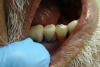

Figure 10: Excess temporary crown material has infiltrated the interproximal spaces; this must be removed and the margins refined before cementation.

Figure 10